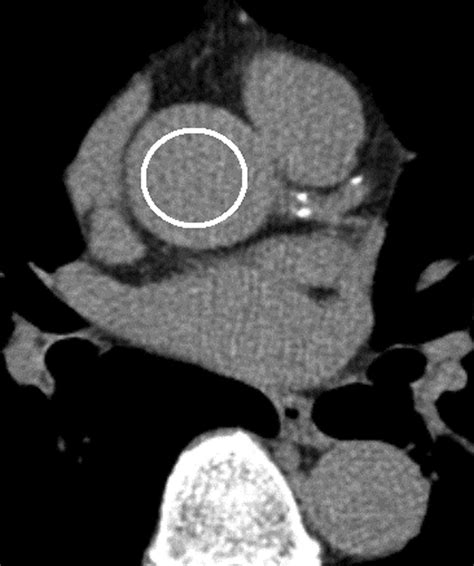

Diagnosing Low Calcium on ECG

Diagnosing low calcium on ECG involves a systematic approach that includes a thorough clinical evaluation and laboratory testing. The following steps are typically involved in the diagnostic process:

• ECG Interpretation: The ECG findings, as discussed earlier, are essential for diagnosing low calcium on ECG. The presence of a prolonged QT interval, T wave abnormalities, ST segment changes, and prominent U waves should raise suspicion of hypocalcemia.